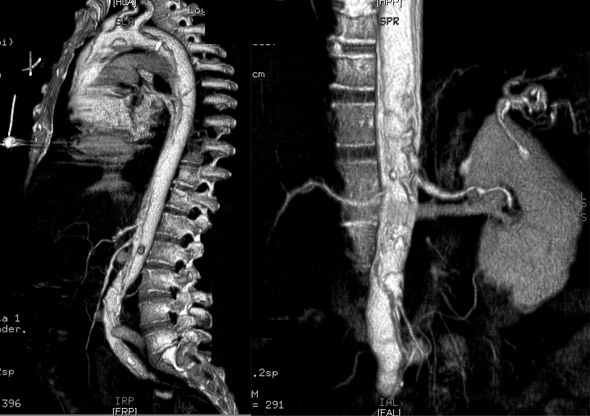

Radiologic Criteria for Dissection in CT scanning:

• The diagnosis of aortic dissection by CT requires the identification of two distinct lumens with a visible intimal flap:

• False lumen

• Flap

• True lumen

• Indirect signs include compression of the true lumen by the false lumen, spiraling of a thrombosed false lumen, displaced intimal calcification, widening of the aortic lumen, and ulcer-like projections of contrast material.

• The advantages of CT include ready availability and the fact that it is a noninvasive procedure.

• It is also helpful in identifying causes of aortic widening other than dissection (such as tumors or periaortic hematomas), and can identify the presence of a pericardial effusion.

• It is disadvantageous in that it cannot identify the presence of aortic insufficiency or delineate coronary arteries.

• Contrast-enhancing CT scanning has a reported sensitivity of 94%, but a specificity of only 87%.

• Current CT scanning techniques improve the accuracy of CT scanning in diagnosing aortic dissection.

• 3D reconstructed images provide remarkable details.

Aortic Dissection CT

Dissection Aorta CT

• Arrowheads: Intimal flap

Dissecting Aneurysm

3D Reconstructed image